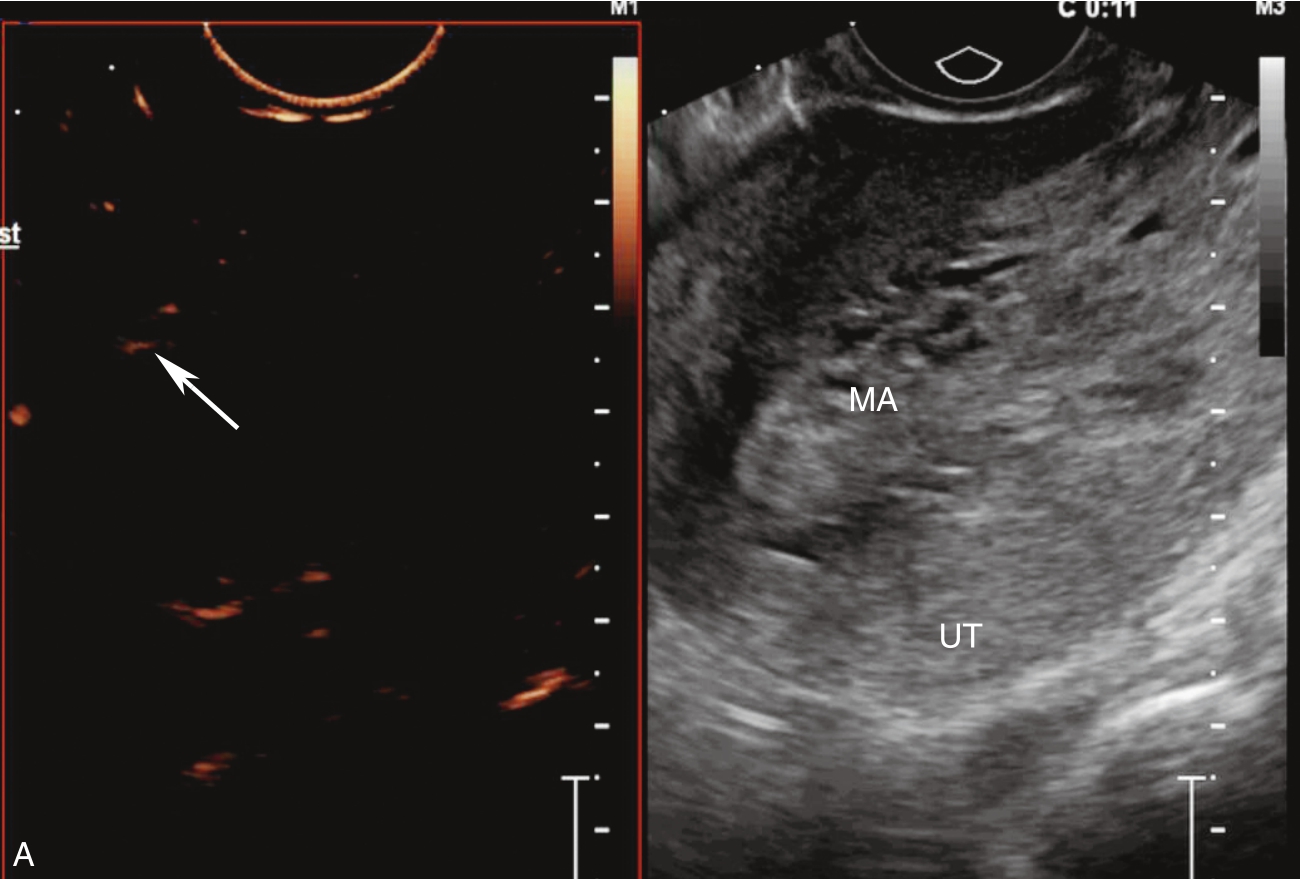

经静脉超声造影见图3-10-2及ER 3-10-1。注入造影剂后11s,宫腔内不均质稍强回声团块开始出现增强(图3-10-2A箭头所示),稍早于子宫肌层增强;注入造影剂后22s,团块根蒂似附着于宫腔上段宫底处(图3-10-2B箭头所示);注入造影剂后26s,宫腔内团块呈高增强,且其内造影剂分布不均匀(图3-10-2C箭头所示);注入造影剂后43s,宫腔内团块造影剂消退晚于子宫肌层(图3-10-2D箭头所示)。

图3-10-2 经静脉超声造影声像图

A.注入造影剂后11s;B.注入造影剂后22s;C.注入造影剂后26s;D.注入造影剂后43s。UT:子宫;MA:肿物。